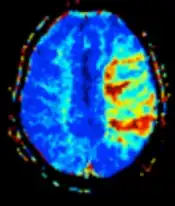

Diffusion weighted (DWI) Conventional DWI Measure of Brownian motion of water molecules.[17] High signal within minutes of cerebral infarction (pictured).[18]

Apparent diffusion coefficient ADC Reduced T2 weighting by taking multiple conventional DWI images with different DWI weighting, and the change corresponds to diffusion.[19] Low signal minutes after cerebral infarction (pictured).[20]

Another application of diffusion MRI is diffusion-weighted imaging (DWI). Following an ischemic stroke, DWI is highly sensitive to the changes occurring in the lesion.[44] It is speculated that increases in restriction (barriers) to water diffusion, as a result of cytotoxic edema (cellular swelling), is responsible for the increase in signal on a DWI scan. The DWI enhancement appears within 5–10 minutes of the onset of stroke symptoms (as compared to computed tomography, which often does not detect changes of acute infarct for up to 4–6 hours) and remains for up to two weeks. Coupled with imaging of cerebral perfusion, researchers can highlight regions of "perfusion/diffusion mismatch" that may indicate regions capable of salvage by reperfusion therapy.